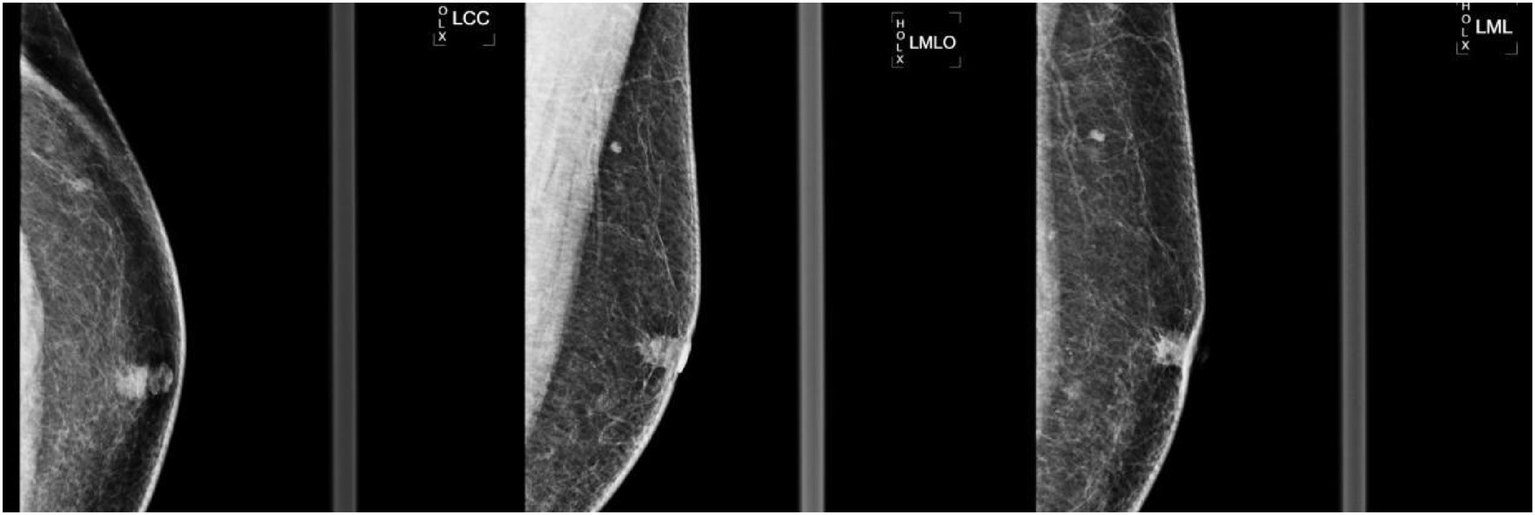

Figure 2

Left breast mammogram in craniocaudal (LCC) mediolateral (LML) and mediolateral oblique (LMO) views. A 10 × 9 mm irregular high-density mass with marked spiculation and architectural distortion was identified in the left subareolar region. The left nipple demonstrated mild inversion (arrow), and no suspicious microcalcifications were noted.